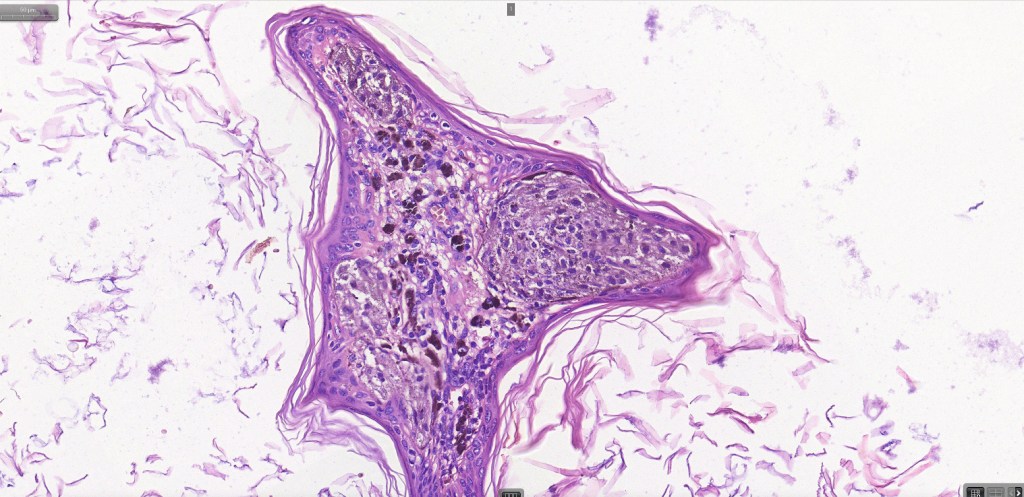

•Large dyscohesive nests with retraction artifact, not restricted to the tips of the epidermal ridges

•Heavy pigmentation (sometimes gray/green)

•Bridging common, often over multiple rete ridges

•Variable atypia (can be marked)